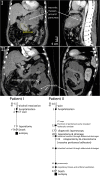

Neutrophils form neutrophil extracellular traps (NETs) of decondensed DNA and histones that trap and immobilize particulate matter and microbial pathogens like bacteria. NET aggregates reportedly surround and isolate large objects like monosodium urate crystals, which cannot be sufficiently cleared from tissues. In the setting of acute necrotizing pancreatitis, massive tissue necrosis occurs, which is organized as pancreatic pseudocysts (1). In contrast to regular cysts, these pseudocysts are not surrounded by epithelial layers. We hypothesize that, instead, the necrotic areas observed in necrotizing pancreatitis are isolated from the surrounding healthy tissues by aggregated NETs. These may form an alternative, putatively transient barrier, separating necrotic areas from viable tissue. To test this hypothesis, we investigated histological samples from the necropsy material of internal organs of two patients with necrotizing pancreatitis and peritonitis accompanied by multiple organ failure. Tissues including the inflammatory zone were stained with hematoxylin and eosin and evaluated for signs of inflammation. Infiltrating neutrophils and NETs were detected by immunohistochemistry for DNA, neutrophil elastase (NE), and citrullinated histone H3. Interestingly, in severely affected areas of pancreatic necrosis or peritonitis, chromatin stained positive for NE and citrullinated histone H3, and may, therefore, be considered NET-derived. These NET structures formed a layer, which separated the necrotic core from the areas of viable tissue remains. A condensed layer of aggregated NETs, thus, spatially shields and isolates the site of necrosis, thereby limiting the spread of necrosis-associated proinflammatory mediators VSports手机版. We propose that necrotic debris may initiate and/or facilitate the formation of the NET-based surrogate barrier. .